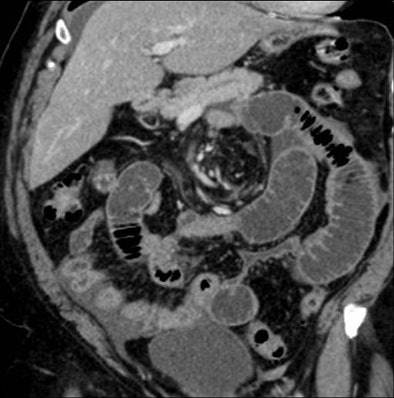

![]() |

| Above, small-bowel obstruction diagnosed with both oral and IV contrast. Below, another patient with small-bowel obstruction diagnosed with IV contrast alone. |